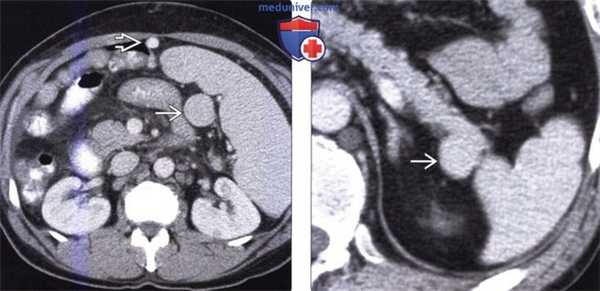

(Слева) На аксиальной КТ с контрастированием визуализируется небольшая добавочная селезенка В округлой формы, расположенная около ворот основной селезенки. Обратите внимание на включения кальция, обусловленные гистоплазмозом, в основной и добавочной селезенке - край -не характерные изменения, которые не требуют дообследования.

(Справа) На аксиальной КТ с контрастным усилением определяется большое объемное образование, тесно прилежащее к хвосту поджелудочной железы и воротам селезенки. Образование было расценено как нейроэндокринная опухоль, при операции было установлено, что образование является добавочной селезенкой (обратите внимание на то, что ее плотность идентична плотности селезенки).

(Слева) На аксиальной КТ с контрастированием, выполненной пациенту с циррозом печени, визуализируется увеличенная (вследствие портальной гипертензии) селезенка. Обратите внимание на большую добавочную селезенку, а также венозные коллатерали. Добавочная селезенка может увеличиваться в размерах аналогично основной.

(Справа) На аксиальной КТ с контрастным усилением определяется гиперваскулярное образование в области хвоста поджелудочной железы, напоминающее островковоклеточную опухоль. Образования в области ворот селезенки могут возникать в хвосте поджелудочной железы, в паренхиме селезенки, либо поражать эти органы вторично.